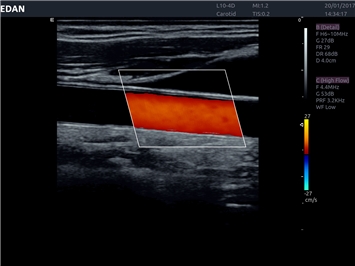

EDAN Acclarix LX4

Расширьте свои представления. Использование усовершенствованной платформой Acclarix система LX4 обеспечивает непревзойденную четкость изображений и интеллектуальный рабочий процесс для всех пользователей, являясь при этом наиболее экономичным решением.

EDAN Acclarix LX4 представляет собой инновационную ультразвуковую систему, построенную на усовершенствованной платформе Acclarix. Сочетание высокого качества визуализации с интеллектуальным рабочим процессом делает эту систему оптимальным выбором для клиник, ценящих эффективность и экономичность.

• Тканевая допплеровская визуализация (TDI)

• Автоматическое измерение толщины интима-медиа

• Сосудистой диагностики

Цветовой допплер:

Да